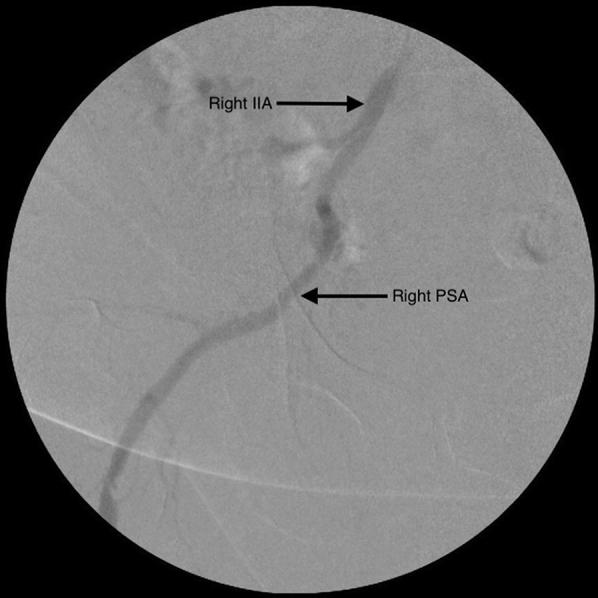

We report a rare case of a persistent sciatic artery in a 59-year-old woman who had presented with unilateral acute limb ischemia. A heparin infusion was started. A right lower extremity arterial duplex ultrasound scan showed an occluded superficial femoral artery and underwent catheter-directed thrombolysis of her right popliteal artery, which was fed by a persistent sciatic artery. After recovery, computed tomography angiography was performed, which confirmed a persistent sciatic artery of the right lower extremity. The patient had presented with thrombotic disease secondary to atherosclerosis of popliteal and tibial arteries, in contrast to the more commonly seen aneurysmal disease with thrombosis.

我们报告了一例罕见的病例,一名59岁女性出现单侧急性肢体缺血,其存在持续性坐骨动脉。开始进行肝素输注。右下肢动脉双功超声扫描显示股浅动脉闭塞,并对由持续性坐骨动脉供血的右腘动脉进行了导管定向溶栓治疗。恢复后,进行了计算机断层血管造影,证实右下肢存在持续性坐骨动脉。与更常见的伴有血栓形成的动脉瘤疾病不同,该患者出现的是继发于腘动脉和胫动脉动脉粥样硬化的血栓性疾病。